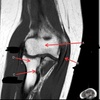

11

Q

What is letter A?

A

ANTERIOR LABRUM

How well did you know this?

1

Not at all

2

3

4

5

Perfectly

12

What is letter B?

BICEPS TENDON (LONG HEAD)

13

What is letter C?

HEAD OF HUMERUS